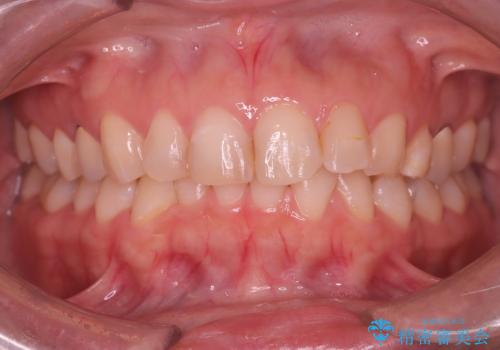

今回の矯正治療では、透明なマウスピース型の装置インビザラインを使用しました。目立たず、取り外しが可能なため、日常生活にほとんど影響なく治療を進めることができました。治療は、緻密に計算された計画に基づき、IPRなどで必要なスペースを確保しながら、下の前歯をスムーズに移動。これにより、長年の悩みであった下の前歯のデコボコが解消され、清掃しやすい、整った歯並びを獲得していただけました。